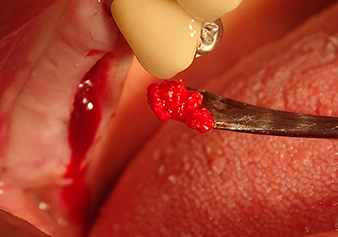

L’insert I2A (diamètre 2,0 mm) est ensuite utilisé pour perforer le plancher sinusien par intermittence et à la plus petite échelle possible. Cette méthode piézochirurgicale spéciale garantit que la membrane de Schneider n’est pas endommagée. Quand le Z25P est utilisé, la membrane est déjà légèrement relevée sous l’effet du fluide de refroidissement délivré via la pointe de l’insert (Fig. 3). Seulement 50 % du fluide de refroidissement sont éjectés afin d'éviter une pression élevée sur le site implantaire.

Préparation et augmentation du site implantaire